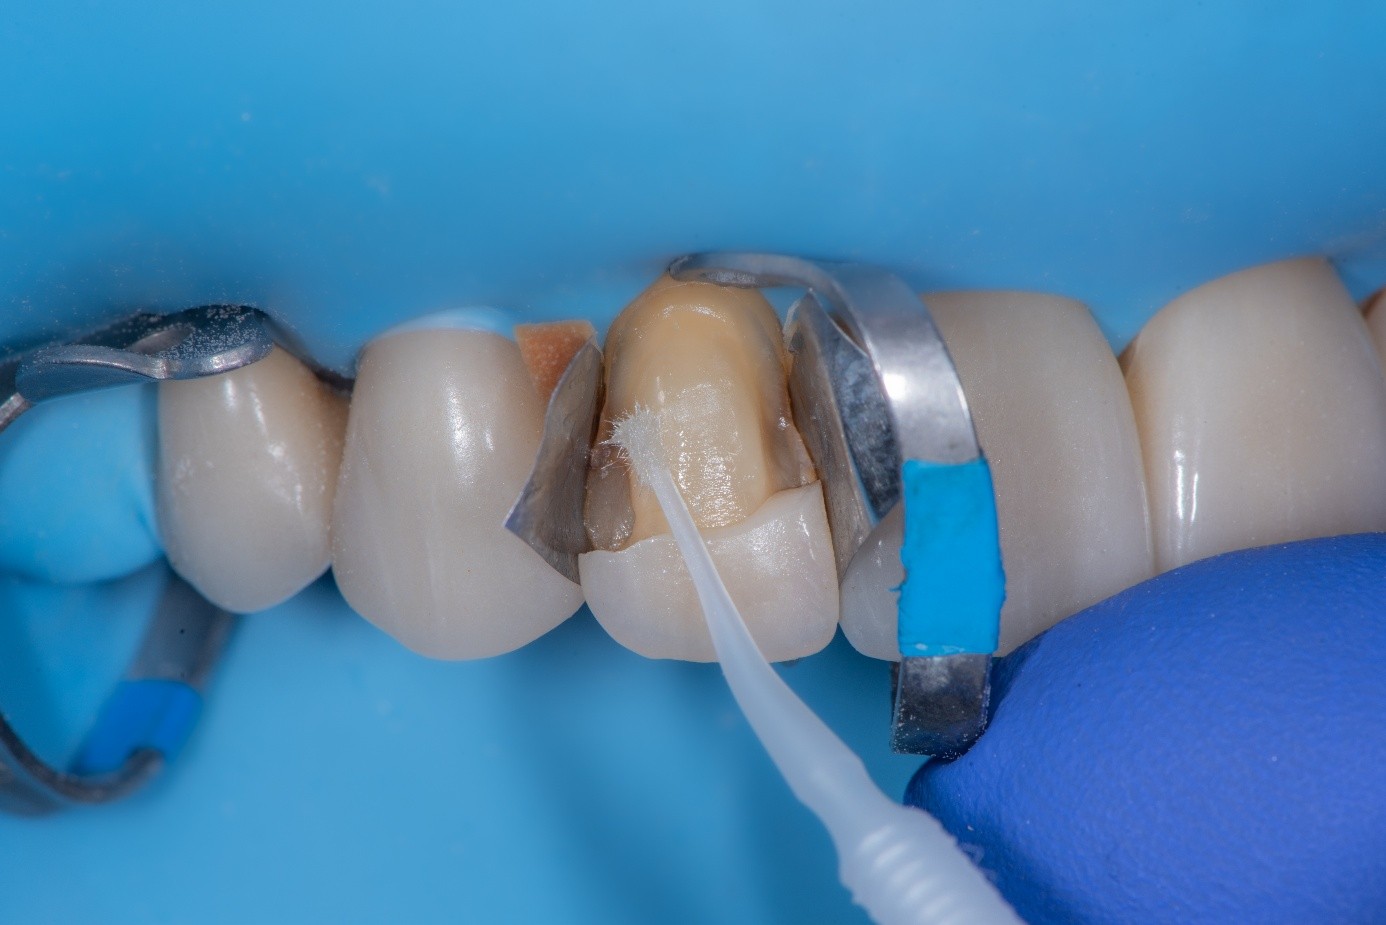

After shade selection and clinical photos, absolute isolation with a rubber dam was achieved. The intaglio surface of the fractured piece was air abraded with glass beads at 2 bars of pressure to remove residual cement. Aluminum oxide powder should be avoided on glass ceramics, as it tends to create microcracks and has shown to decrease bonding strength (Figure 4 and Figure 5).4 The fractured piece was etched with 9% hydrofluoric acid for 120 seconds followed by thorough rinsing for 20 seconds, then scrubbed with 37% phosphoric acid for 60 seconds and placed in an ultrasonic bath for four minutes in distilled water, rinsed, dried, and treated with silane to promote chemical bonding and heat treated at 100 °C for 5 seconds (Figure 6).5,6 The combination of the phosphoric acid scrub and the ultrasonic bath after HF etching helps to remove any calcium salt residues created during HF etching.

(3.) Fractured ceramic piece of the upper lateral incisor showing adhesive and cement remnants on the inner surface. (4. and 5.) At 100X magnification, the glass beads

Figure 3

(4.) appear perfectly round and smooth, lacking any sharp edges, making them ideal for cleaning glass-ceramic surfaces without causing microcracks. In contrast, aluminum oxide

Figure 4

(5.) particles show sharp, angular edges that can induce microcracks or surface damage during cleaning.